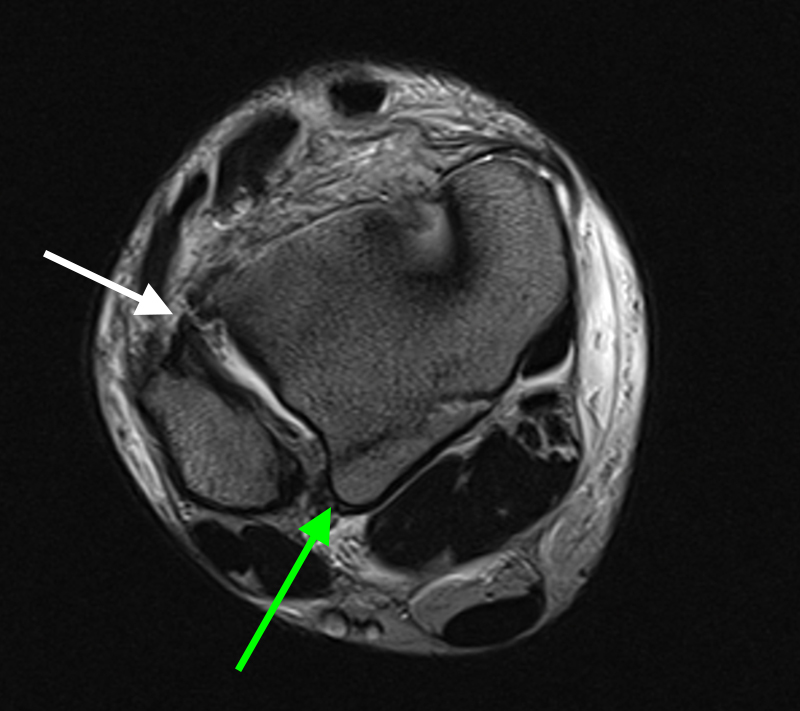

Magnetresonanztomographie (MRT)

Die Magnetresonanztomographie stellt aktuell den Goldstandard in der Diagnostik von Syndesmosenverletzungen dar (Szeimies 2013). Beschrieben sind eine Sensitivität von 100% und eine Spezifität von 93% bei Verletzungen des AITFL, sowie eine Sensitivität und Spezifität von 100% bei Verletzungen des PITFL. Darüber hinaus ermöglicht das MRT weitere ligamentäre, chondrale oder intraossäre Verletzungen zu detektieren. Bei chronischen Syndesmosenverletzungen sollte eine MRT-Diagnostik mit Kontrastmittel (KM) intravenös durchgeführt werden, da diese eine höhere Spezifität und Sensitivität im Vergleich zur nativen MRT-Bildgebung aufweist. Durch die zusätzliche Gabe von KM können durch eine Mehranreicherung des KM im Bereich der Syndesmose Rückschlüsse auf das Vorhandensein einer chronische Instabilität gezogen werden 41.